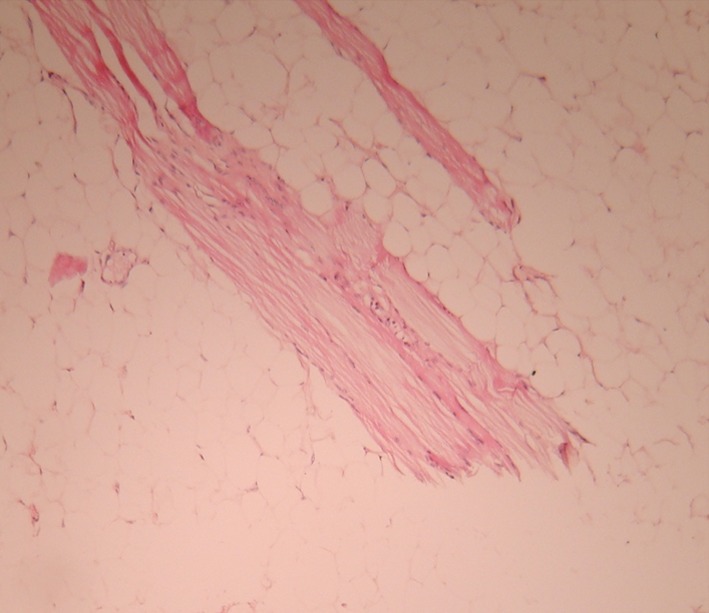

The surgical excision of the mass was done under general anesthesia. A midline, vertical mucosal incision was made directly over the crest of mass. The mucosa was dissected laterally to expose the superior aspect of the mass (Fig. 4). Extreme caution was taken and only blunt dissection was carried out throughout the procedure to prevent damage to the Wharton’s duct, lingual nerve, and sublingual gland. This yielded an unexpectedly soft, yellowish lobulated mass measuring 3.7 × 3.3 × 2.2 cm (Fig. 5). The classical sight of an adipose tissue coupled with a capsule surrounding its periphery reclassified our diagnosis as lipoma. The mass shelled out easily, with no adhesions to the surrounding structures. As the mass was in the submucosal plane, none of the vital structures in the floor of the mouth such as lingual nerve, sublingual gland and Wharton’s ducts were encountered during the dissection. After achieving good hemostasis the mucosal layer was closed together with absorbable sutures. Gross histopathological examination revealed round to oval matured fat cells (with peripherally placed nucleus) arranged in lobules separated by thin cords of fibers. Numerous striated muscles and few blood vessels containing lymphocytes and mast cells were evident. This was consistent with the diagnosis of a simple classical lipoma as shown (Fig. 6). Healing was uneventful. No recurrence was observed at 1 year follow-up.

Fig. 6.

Histopathology appearance showing round to oval mature fat cells

Histopathological examination of the lesion gives the definite diagnosis. Histopathologically lipomas can be classified as (1) classical lipoma; (2) lipoma variants, such as angiolipoma, chondroid lipoma, myolipoma and spindle cell/pleomorphic lipoma, all with specific clinical and histological features; (3) hemartomatous lesions; (4) diffuse lipomatous proliferations; and (5) hibernoma [13]. In the present case, histopathologically all the features were suggestive of simple classical lipoma.